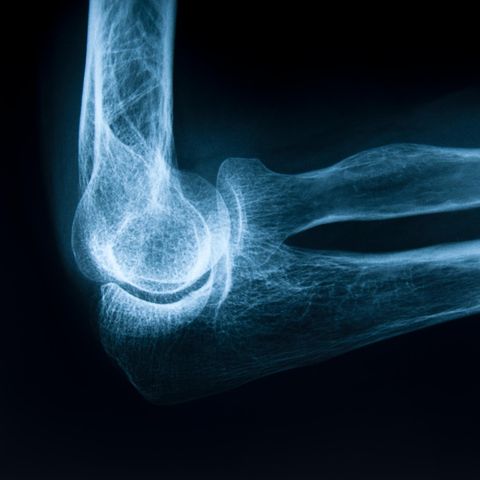

Osteoporose ist eine Knochenstoffwechselstörung, bei der Teile der Knochenstruktur abgebaut werden. Dadurch wird der Knochen dünner, poröser und instabiler; die Folge sind vermehrte Knochenbrüche, auch ohne Stürze und Unfälle.

Anfangs verläuft die Erkrankung oft ohne besondere Symptome. "Ein deutliches Alarmzeichen ist, wenn sich die Körpergröße um mehrere Zentimeter verringert, weil Wirbelkörper zusammengebrochen sind", sagt Eichhorn. Im weiteren Verlauf kommt es zu Schmerzen und Bewegungseinschränkungen durch erste Knochenbrüche. Knackt ein poröser Oberschenkelhals, verursacht das massive Schmerzen. Dazu braucht es keinen Sturz oder Unfall, ein leichtes Wegrutschen eines Beines kann bereits genügen.

"Ab 60 Jahren sollte man die Knochendichte regelmäßig messen lassen", rät Eichhorn. Die Diagnose ist schnell, schmerzfrei und eine Kassenleistung. Bundesweit gibt es rund 800 Osteologen, Knochenspezialisten, die auf entsprechende Untersuchungen spezialisiert sind. Unter https://osteoporose-verstehen.de/expertensuche/ finden Patienten und Angehörige Osteologinnen und Osteologen in der Nähe ihres Wohnortes. Zusätzlich zur Knochendichtemessung veranlassen sie eine Laboruntersuchung und fragen Patientinnen nach spezifischen Risikofaktoren. Sie ermitteln einen sogenannten Therapieschwellenwert, der angibt, mit welcher Wahrscheinlichkeit ein Knochen innerhalb von drei Jahren bricht, ohne dass es dabei zu einem Sturz oder einem Unfall gekommen sein muss.

Mehr als 800.000 Frakturen pro Jahr gehen auf Osteoporose zurück. Die überwiegende Zahl von ihnen sind Frakturen des Oberschenkelhalses. Eichhorn warnt: "Es ist ein Irrtum, zu glauben, dass der Oberschenkelhalsbruch ab 75 Jahren 'normal' ist." Das Fatale: Rund 20 Prozent der Oberschenkelhalsbrüche verlaufen tödlich, 30 Prozent der Betroffenen können sich danach nicht mehr alleine versorgen, sondern werden zum Pflegefall. 30 Prozent der Betroffenen erleiden zudem im ersten Jahr der Erkrankung eine zweite Fraktur, wenn die Osteoporose unbehandelt bleibt. Denn noch immer versäumen es Kliniken häufig, Patienten nach einer OP des Oberschenkelhalses auf ihre Knochendichte zu untersuchen. Durch die Behandlung im Krankenhaus, die Operation und die anschließende Reha entstehen 13,8 Milliarden Euro an Kosten für die gesetzlichen Krankassen.